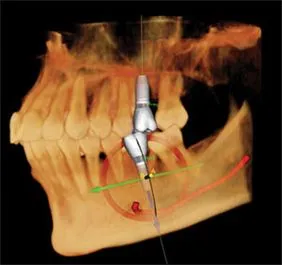

The current emerging standard of care in dentistry and dental implantology is the use of three dimensional x-ray studies. The 3-D images allow the doctor to collect the needed and highly valuable diagnostic information so they can best plan and deliver dental and surgical care.

3D Imaging Technology provides three-dimensional imaging to the dental community, right in the practice office. The system offers active sagittal, coronal, and axial viewing and manipulation. It enhances diagnosis and treatment planning by providing more accurate imaging. Using the 3-D mapping tool, dental professionals can easily format and select desired slices for immediate viewing. Cone Beam imaging delivers quicker and easier image acquisition a typical scan takes only 20 seconds.

The diagnostic images from the i-CAT scanner can be easily converted into a third party software (i.e. Simplant, Nobel guide, Dolphin, etc.) for pre-surgical evaluation and computer guided surgery. The doctor will receive a viewable animation to help him measure and analyze your case from every aspect. The data can also be used to fabricate your surgical guides.